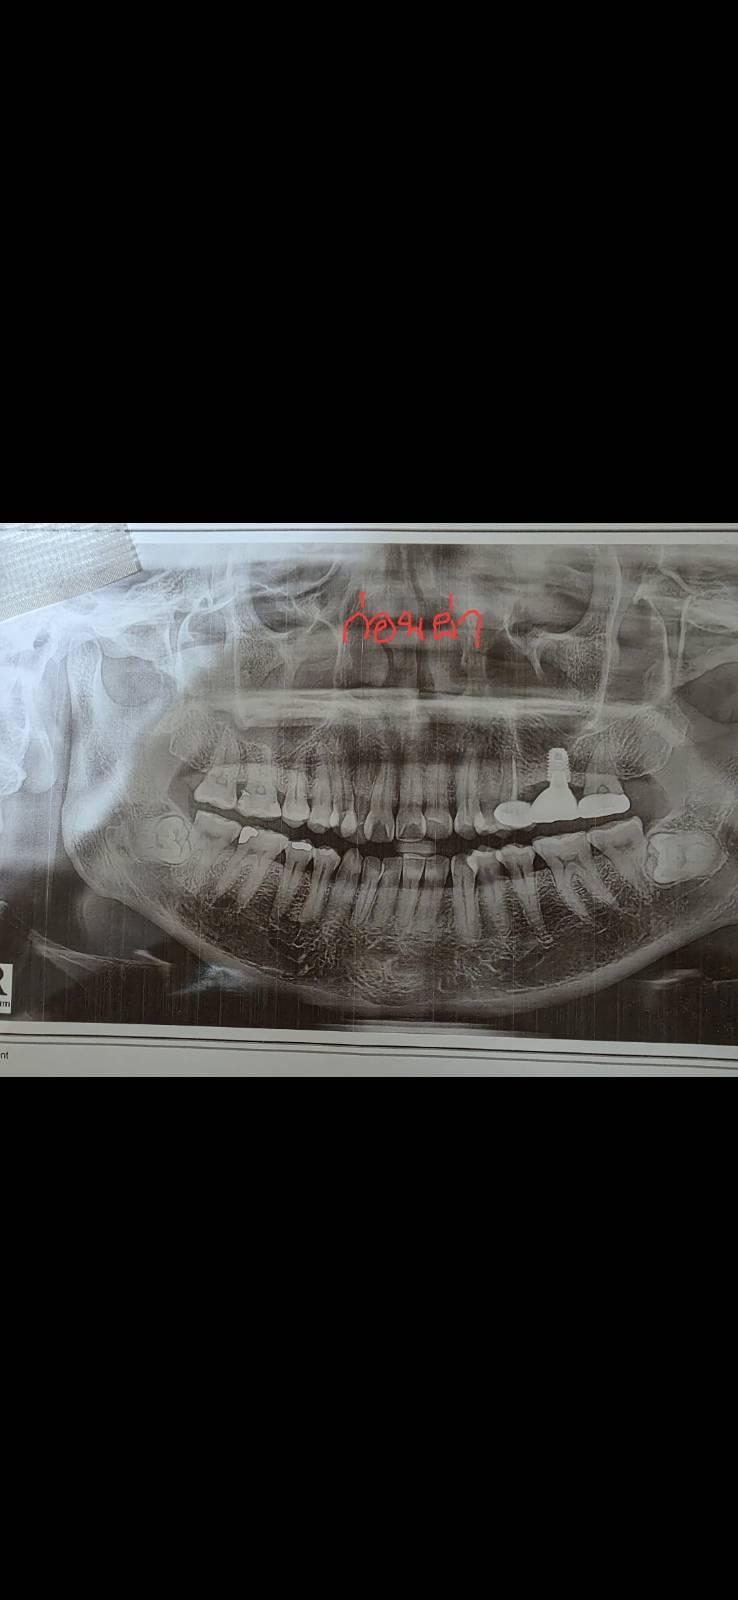

รบกวนผู้รู้ช่วยดูฟิล์มให้ทีค่ะ #ผ่าฟันคุด

อยากทราบว่าหลังผ่าฟันคุดออกข้างนึงแล้ว เศษขาวๆ ที่วงไว้ ใช่เศษฟันแตก (มีการกรอฟันระหว่างผ่าฟันคุดอยู่หลายครั้ง) ที่หลงเหลืออยู่หรือเปล่าคะ